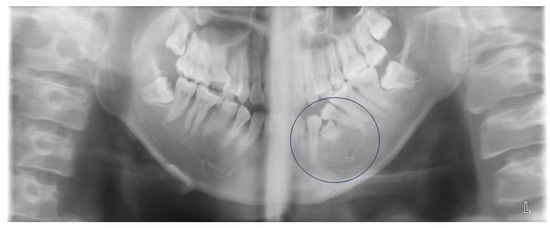

We performed panoramic tomography, with his father and a dentist holding his face and body firmly for stability (Figure 1). We performed this panoramic tomography as we suspected that the cause of his problem might be located deep in the alveolar bone, which would not be revealed by a dental X-ray. The X-ray image showed what looked like the crown of the first deciduous molar in his left mandibular alveolar bone. However, confirmation that it was a submerged first deciduous molar could not be obtained; in any case, it was hard tissue and not an edema.

Figure 1. Panoramic X-ray image taken at the first visit to Nippon Dental University Hospital. This image revealed the presence of hard tissue between the first and second mandibular premolars (indicated by the circle).